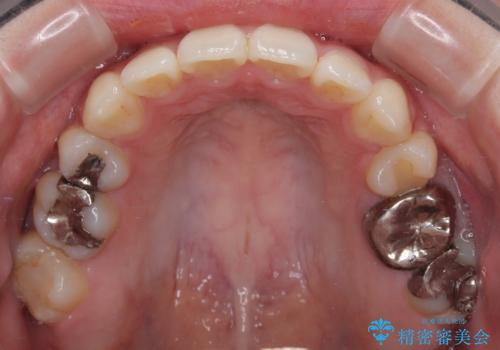

- 下の前歯のデコボコと、口元の突出感を改善したいと来院された患者様です。

突出感の強い上顎前歯をしっかりと後方移動させるため、上顎の裏側の補助装置(リンガルアーチ)とアンカースクリューを併用しています。

上下左右の第一小臼歯を抜歯して、目立ちにくいワイヤー装置で矯正を行いました。

上下の保定用マウスピースの他に、デコボコの強かった下顎前歯にはワイヤーで保定をしています。